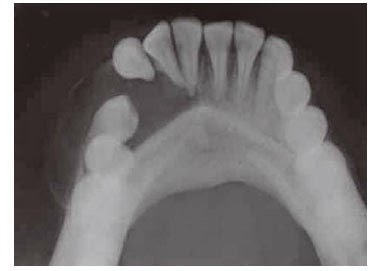

- Radiographically adenomaroid odontogenic tumor presents a well-defined , unilocular,radiolucent area,which is often enclosing a tooth or tooth-like stucture.

- Multiple small,radiopaque foci of varying radiodensity may be predent inside the lesion .

- Expansion of the distrotion of the cortical plates and displacement of the roots of the adjoining teeth are sometime seen.

- The border of the lesion is not well corticated and it consistently engulfs the impacted tooth including its root.This feature differentiates adenomataid adontogenic tumor from dentigerous cyts,since the later lession encloses only the crown portion of on impacted tooth.